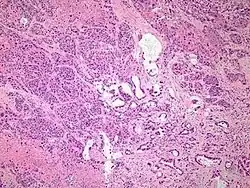

Micrograph of an adenosquamous carcinoma of the lung. The adeno- or glandular component is on the left of the image and the squamous component on the right of the image. H&E stain.

Light microscopy shows a combination of gland-like cells and squamous epithelial cells.[4] On immunohistochemistry, it is typically positive for CK5/6, CK7 and p63, and negative for CK20, p16 and p53. On genetic testing, KRAS and p53 are typically altered.[4]